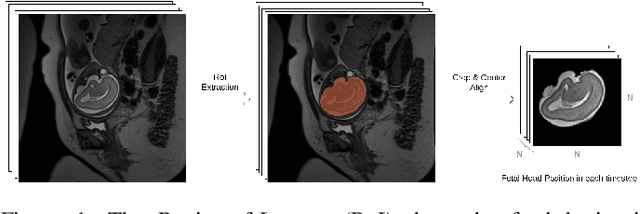

Fetal magnetic resonance imaging (MRI) is challenged by uncontrollable, large, and irregular fetal movements. Fetal MRI is performed in a fully interactive manner in which a technologist monitors motion to prescribe slices in right angles with respect to the anatomy of interest. Current practice involves repeated acquisitions to ensure diagnostic-quality images are acquired; and the scans are retrospectively registered slice-by-slice to reconstruct 3D images. Nonetheless, manual monitoring of 3D fetal motion based on displayed 2D slices and navigation at the level of stacks-of-slices (instead of slices) is sub-optimal and inefficient. The current process is highly operator-dependent, requires extensive training, and significantly increases the length of fetal MRI scans which makes them difficult for pregnant women, and costly. With that motivation, we presented a new real-time image-based motion tracking technique in MRI using deep learning that can significantly improve state of the art. Through a combination of spatial and temporal encoder-decoder networks, our system learns to predict 3D pose of the fetal head based on dynamics of motion inferred directly from sequences of acquired slices. Compared to recent works that estimate static 3D pose of the subject from slices, our method learns to predict dynamics of 3D motion. We compared our trained network on held-out test sets (including data with different characteristics, e.g. different age ranges, and motion trajectories recorded from volunteer subjects) with networks designed for estimation as well as methods adopted to make predictions. The results of all estimation and prediction tasks show that we achieved reliable motion tracking in fetal MRI. This technique can be augmented with deep learning based fast anatomy detection, segmentation, and image registration techniques to build real-time motion tracking and navigation systems.